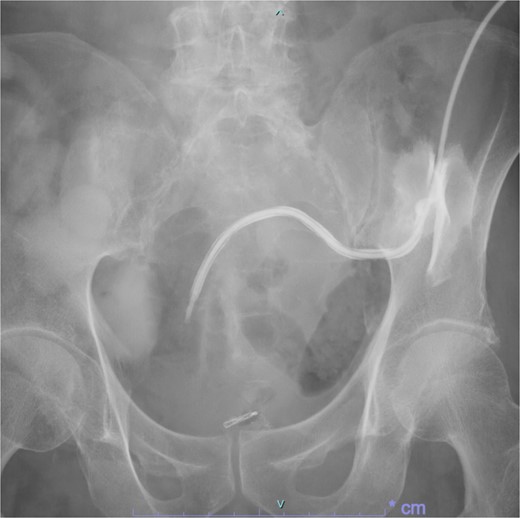

Following reoperation, although drainage led to shrinkage of the fistula, it persisted after 2 months (Fig. 2). Hence, we decided to close the fistula using endoscopic clips. Gastrografin was injected through the drain under colonoscopy and radiography, and bleeding was observed at the suspected fistula orifice, which was provisionally clipped using a MANTIS clip. Gastrografin was injected again, and definitive clipping was completed confirming the successful fistula closure (Fig. 3). The patient was discharged after 2 days. The drain was withdrawn about 3 cm on day 9 after discharge. On day 15, gastrografin injection under radiography revealed recovery of the fistula (Fig. 4). Thereafter, the drain was withdrawn cautiously about 2 cm every 2–3 days to prevent residual fistula formation and removed completely on day 29. Ileostomy closure was performed 6 months after the initial surgery. The patient was discharged without complications on postoperative day 7.

On day 15 after clipping, gastrografin injection under radiography reveals the fistula tends to recover.